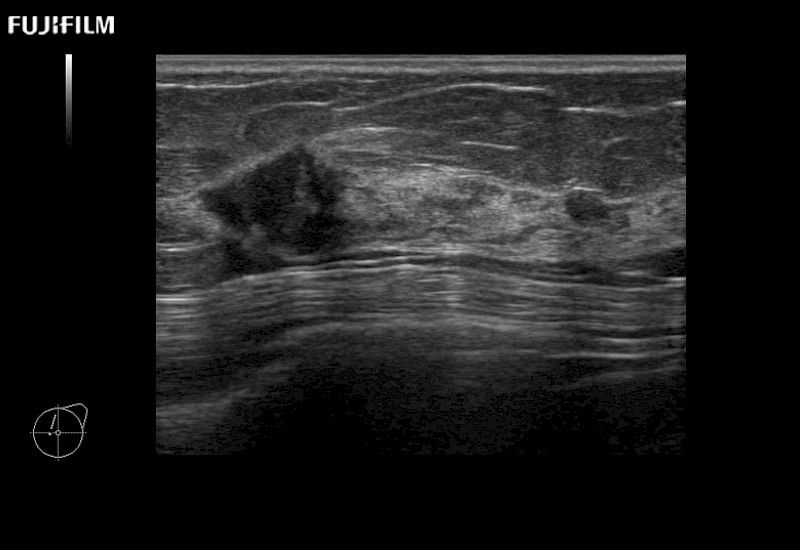

Linear array side-fire “T” transducer for open surgical procedures.

Main Specifications: